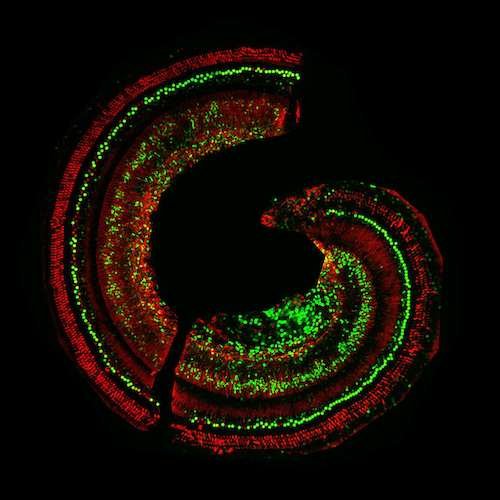

AAV-GFP Targeted Expression in Cochlea of C57 Mice

Laser confocal scanning microscopy (LCSM)